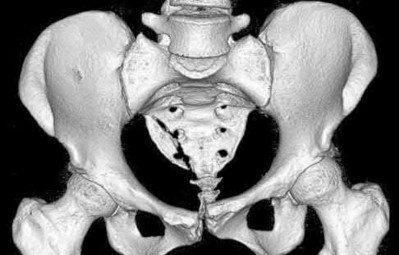

Which of the following associated type acetabular fracture patterns is defined based on the fact that all articular segments are detached from the intact portion of the ilium, which remains attached to the sacrum through the sacroiliac joint?

Corrent answer: 5

There are 5 simple and 5 associated fracture types according to the classification system created by Judet and Letournel. The key feature which distinguishes both column fractures from other associated types is that all articular segments are detached from the intact portion of the ilium, which remains attached to the sacrum through the SI joint.

Although the transverse plus posterior wall, T-shaped, and anterior plus posterior hemi-transverse fractures all show involvement of the anterior and posterior columns, they are not “both columns” because a portion of the

articular surface remains in its normal position, attached to intact ilium.

The intact ilium is responsible for the "spur sign" noted most prominently on the obturator oblique radiograph.

Illustration A demonstrates the 10 types of acetabular fractures as created by Judet and Letournel. Illustration B is an example of a both column acetabular fractures as seen on the obturator oblique radiograph.